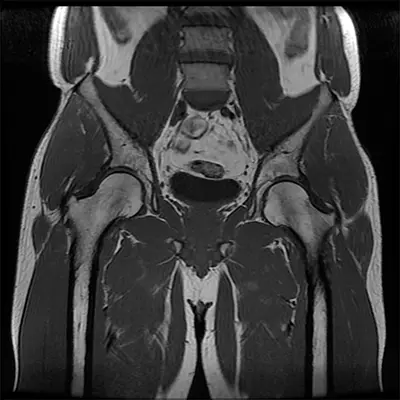

Diagnosis of Ligamentum Teres Tears

Diagnosis typically involves a combination of medical history, physical examination, and imaging:

- MRI Scan: Detects soft tissue damage and can reveal LT tears.

- CT Scan: Provides detailed cross-sectional images of bones and soft tissues.